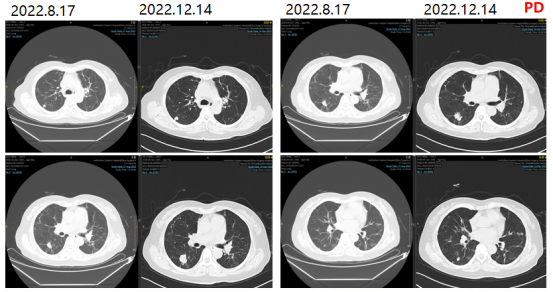

2022-12-14复查胸部CT提示两肺多发转移瘤,较前进展。PFS3:7月。

图5影像学复查结果

2022.12.14影像学复查结果